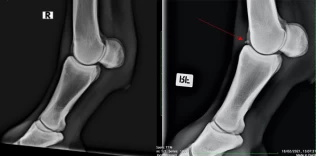

Veterinær Siggi Sigurdsson er spesielt interessert i halthet og hestens bevegelsesapparat. Bildet til venstre er kun et illustrasjonsfoto og har ingen direkte tilknytning til saken. Foto: Adobe Stock / Bjerke Dyrehospital